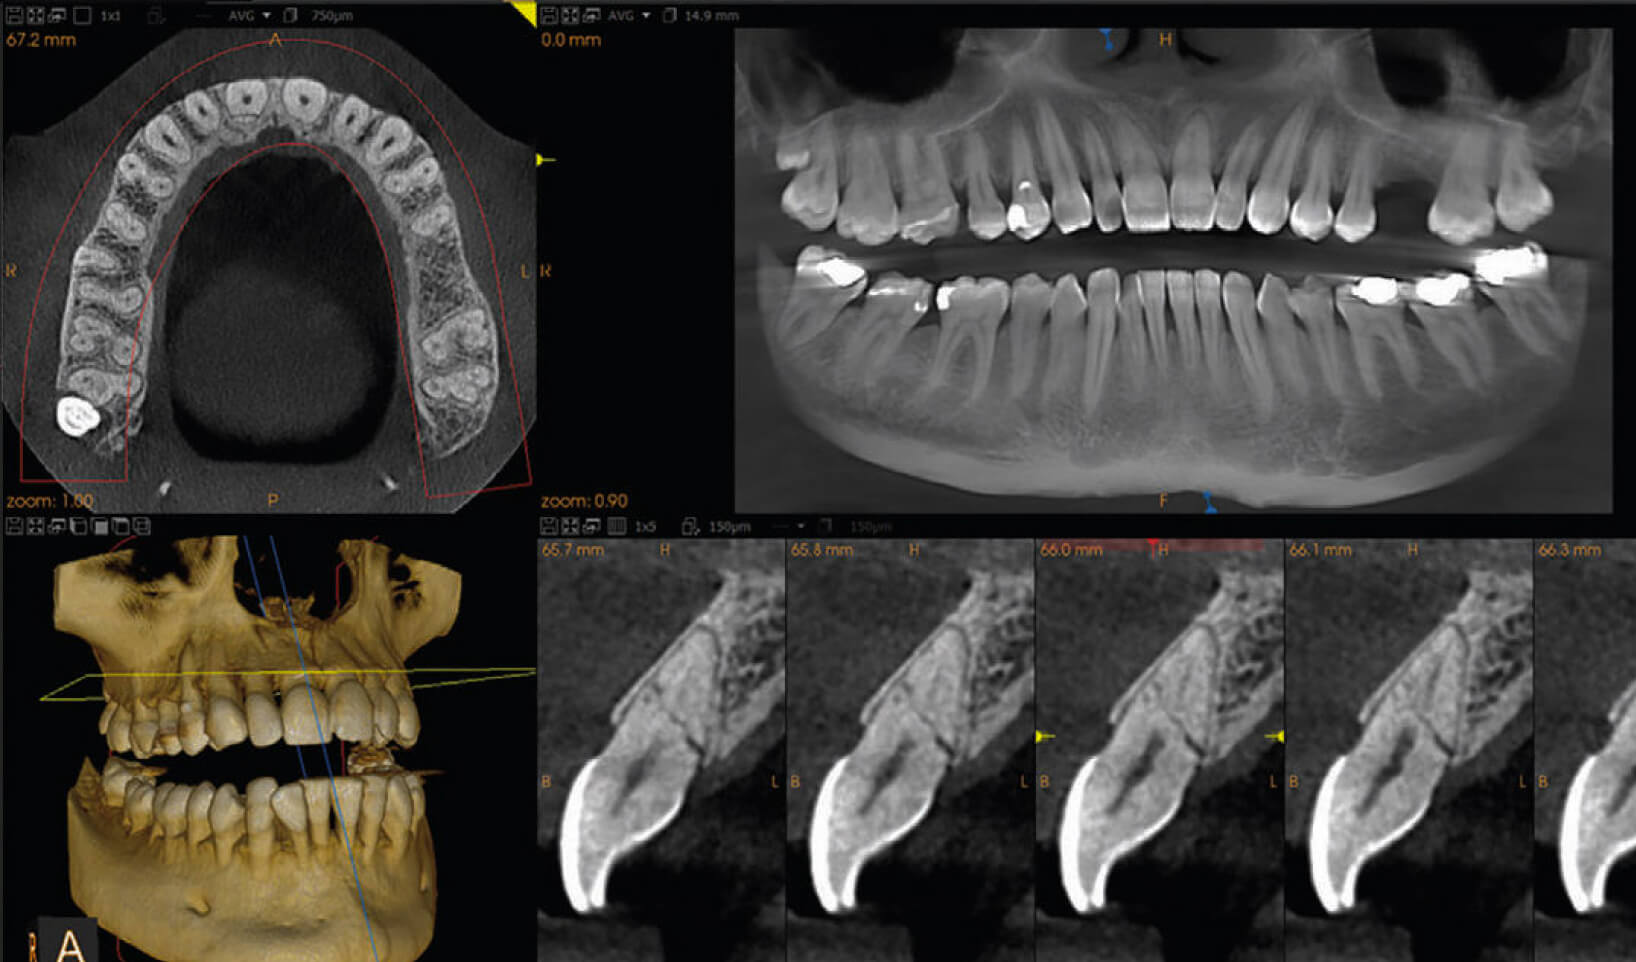

What is it?

Cone Beam CT (CBCT) scans are a way for a dentist to get a vivid 3D image of the intricacies of a patient’s teeth and gums without having to undertake exploratory/invasive treatment procedures to try and ascertain what lies “beneath the surface”.

They are a state-of-the-art alternative to more traditional intra-oral x-rays, which show a two-dimensional image as opposed to the three-dimensional image created by a CBCT scan.

A CBCT scan is an excellent, state-of-the art diagnostic tool that is well-suited to patients whose dental issue is not clear-cut. Much of what happens to a tooth is going on beneath the surface, and while skilled experts can often hypothesize with a great degree of skill about a patient’s dental issue, a CBCT scan removes all of the guesswork. CBCT scans are very often used during endodontics to ensure that root canal treatment is indeed required.

The team at The Endodontic Clinic are highly proficient in this relatively new way of diagnosing dental conditions, and are able to pinpoint the scan down to a very specific part of the mouth – thus limiting radiation to an incredibly small area.

The CBCT machine is similar to the CT scanner seen in hospitals, only much more compact. The 3D image it creates provides vital insight into the insides of the tooth and the area surrounding it, and can help identify tiny fractures, missed canal anatomy, diseases of the jaw and more.